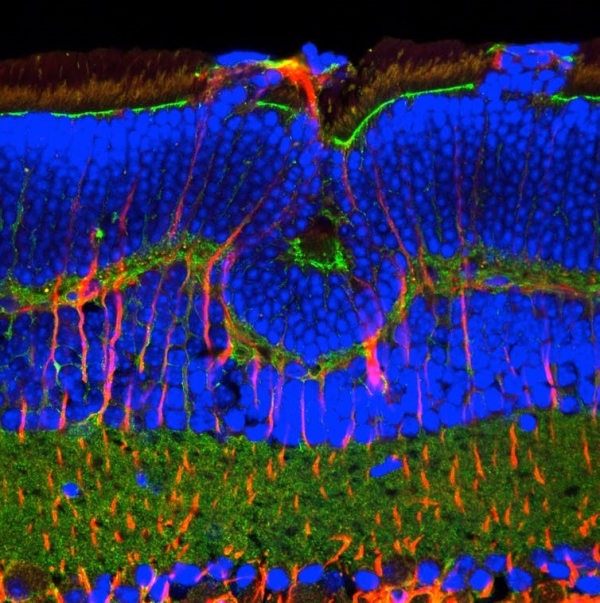

在分子分界的另一边。电子显微照片(2013)。(图片来自:Andrea Rassell, Author provided (No reuse))

共聚焦显微镜成像是利用荧光染料(商业化生产的带有荧光分子的抗体),与生物样本中细胞或组织蛋白特异性结合的一门技术。。荧光分子可以被显微镜的激光激发,发射可见光,并通过光电探测器或照相机成像。在这个大鼠视网膜的例子中,荧光分子靶向了不同的细胞表面蛋白,带有不同荧光分子的抗体用来区分视网膜中的不同细胞类型,揭示了组织的分层结构。这张图像是荧光分子的照片,并不是组织本身的照片。